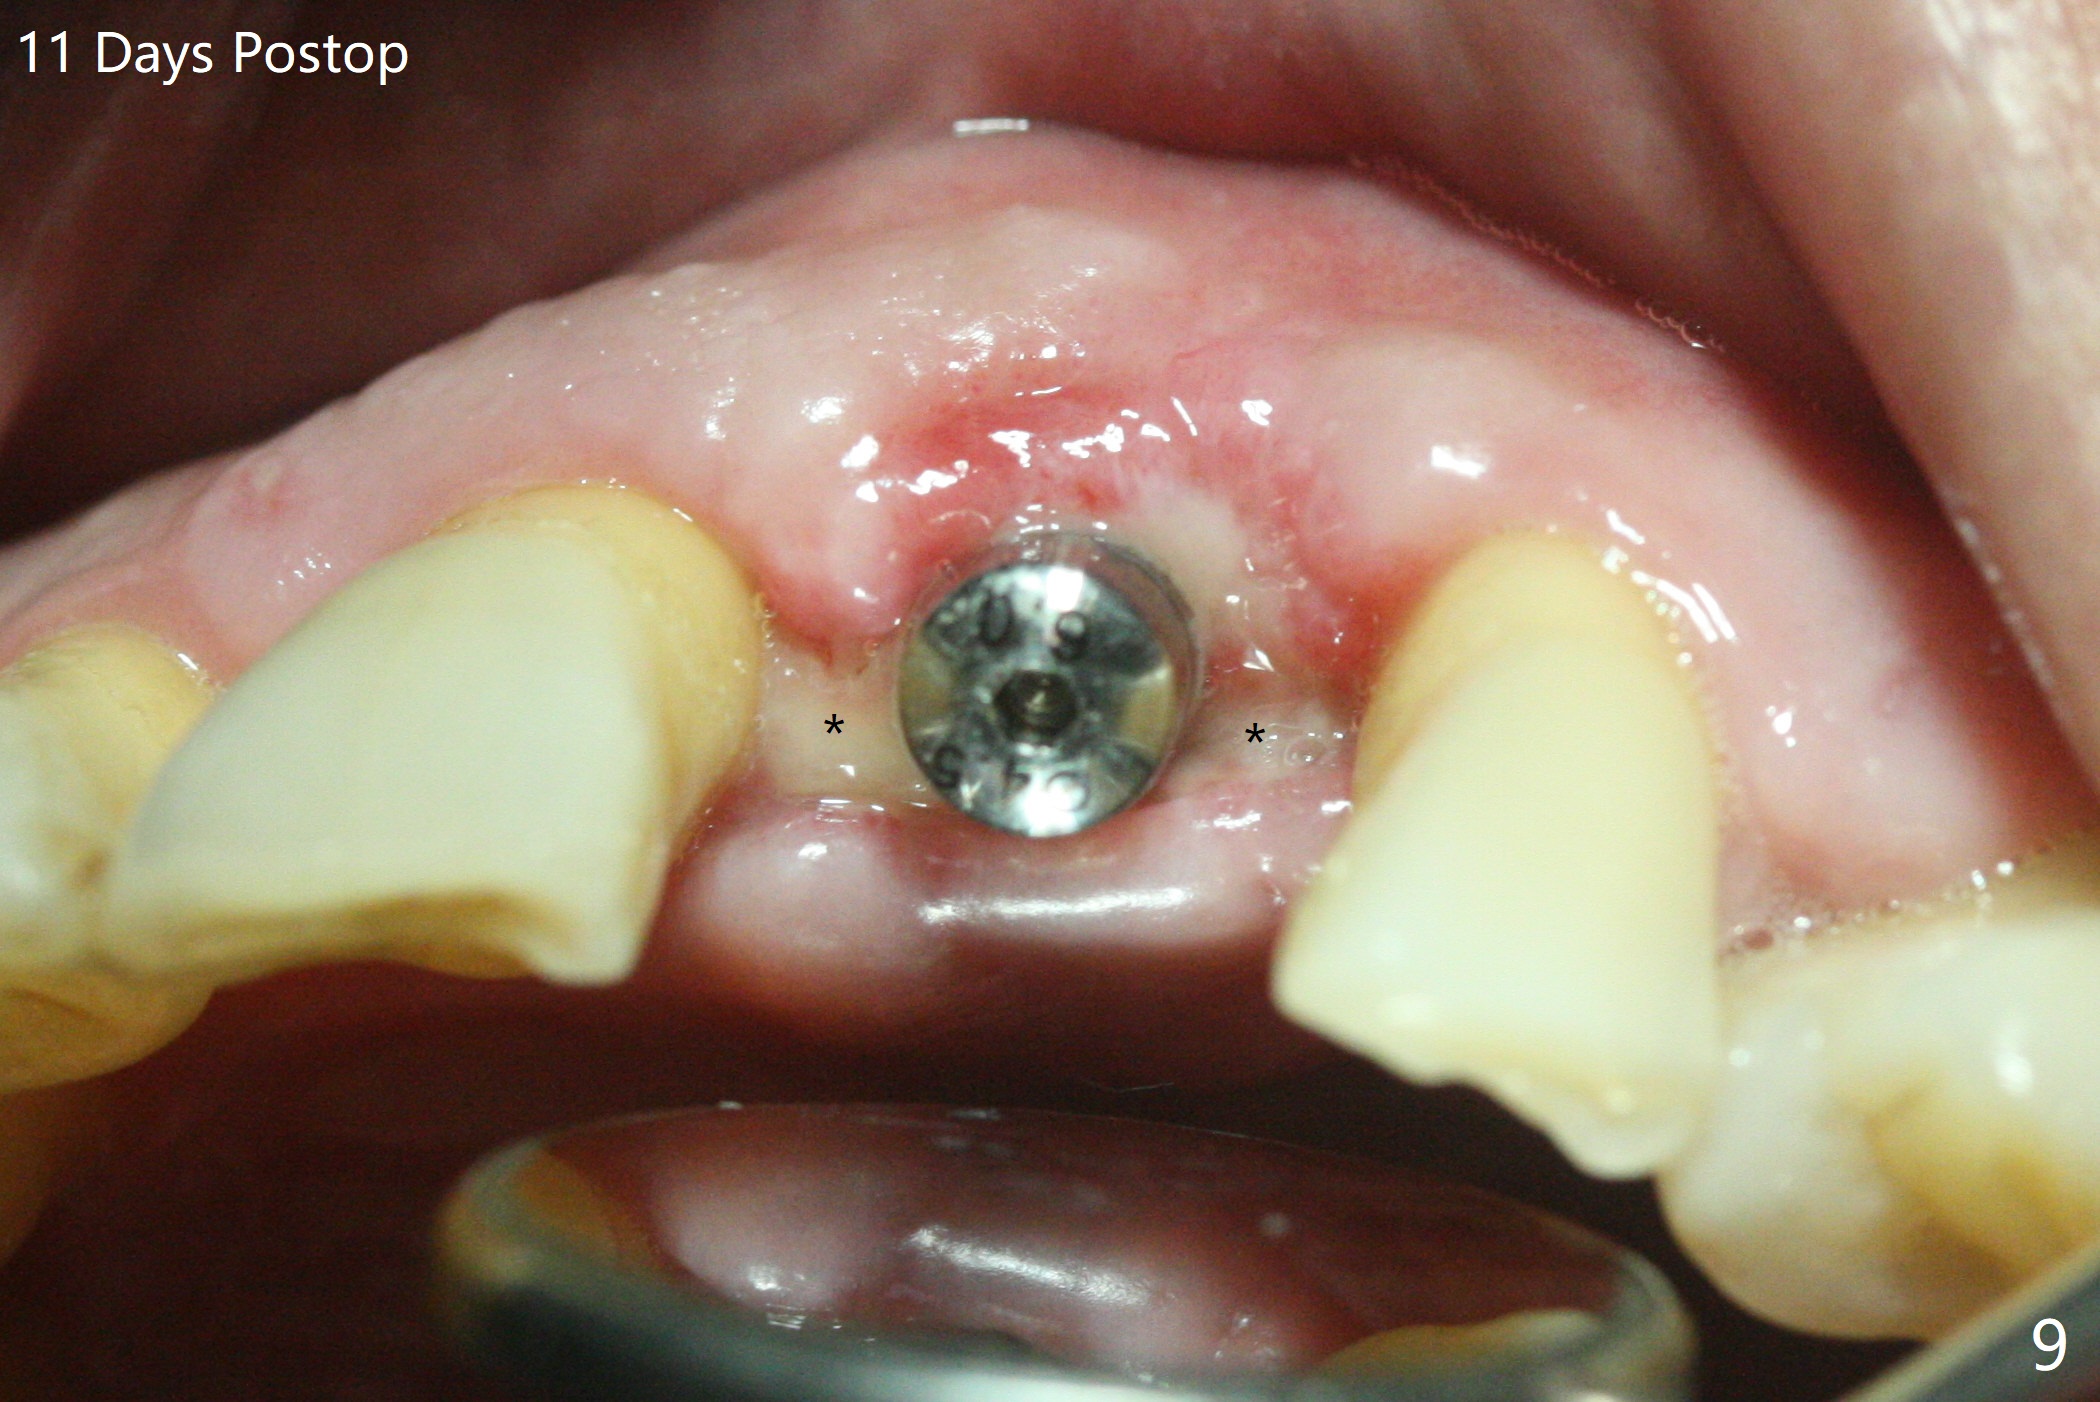

左上1(图一)拔除,植骨,使用带钛架不可吸收膜(图二)后十个月准备植牙(图三),在没有术中根尖片指导下(导板习惯),在牙槽嵴正中开始钻洞,第一个钻头最后一两个毫米觉得有突破感,但是颊侧舌侧没有穿孔,然后植入3.5x11.5毫米植体(图五,扭力>35 Ncm),术后射线表明植体接近切牙管(图四:*)。考虑到病人要离城,颊侧第一螺纹暴露(图六),舌侧骨板薄(图五),植骨,放置愈合基台(图七)。 术后十一天CT显示植体没有侵犯切牙管(图八:I);植体颊侧骨粉(箭头)似乎可以解释颊侧饱满(图九)。第二原因是减张缝合,胶原膜暴露(*),而下面骨粉没有暴露,以后伤口应该是二期愈合。